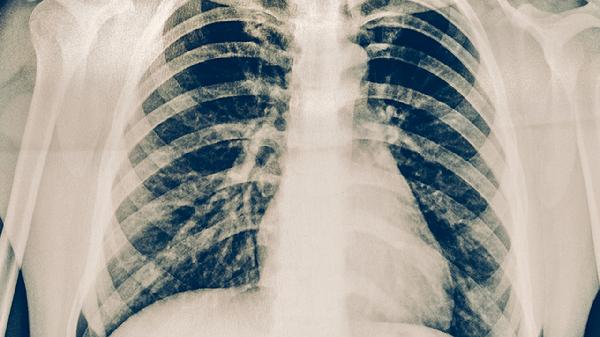

肺結(jié)核病的飲食調(diào)養(yǎng)原則主要有保證優(yōu)質(zhì)蛋白攝入、補(bǔ)充維生素和礦物質(zhì)、選擇易消化食物、避免刺激性食物、保持規(guī)律飲食等。合理的飲食有助于改善營(yíng)養(yǎng)狀況,增強(qiáng)機(jī)體抵抗力,促進(jìn)疾病康復(fù)。